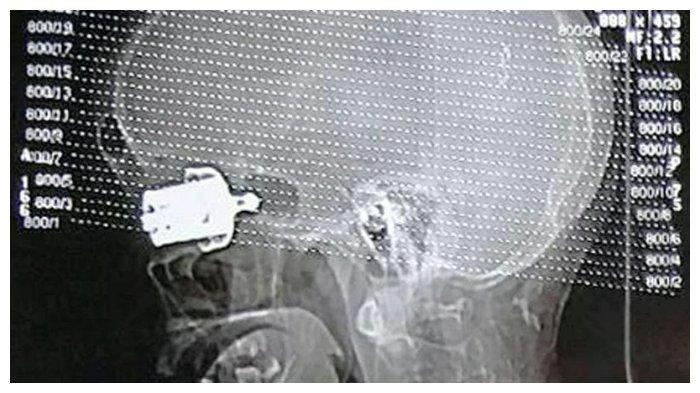

Hasil ronsen Munda Birsi yang kehilangan matanya karena panci presto

Dilansir TribunWow.com dari mirror.co.uk, Selasa (10/9/2019), peluit yang terbuat dari besi itu bahkan menembus hingga ke bagian tengkorak Munda Birsi (57).

Diketahui bahwa para dokter merasa kesulitan saat akan mengeluarkan peluit itu dari mata Munda karena menembus bagian matanya terlalu dalam.

Bahkan peluit itu tidak terlihat lagi dari luar, walapun begitu tim dokter berusaha untuk mengeluarkan potongan logam itu dengan perlahan dari mata Munda.

Pada akhirnya tim medis dari Rumah Sakit Bhagwan Mahavir Medica Super Speciality, Jharkhand berhasil mengeluarkan peluit besi itu dan menyelamatkan nyawa Munda.

Namun Munda harus mengikhlaskan mata kirinya tidak bisa melihat kembali karena luka yang terlalu parah.